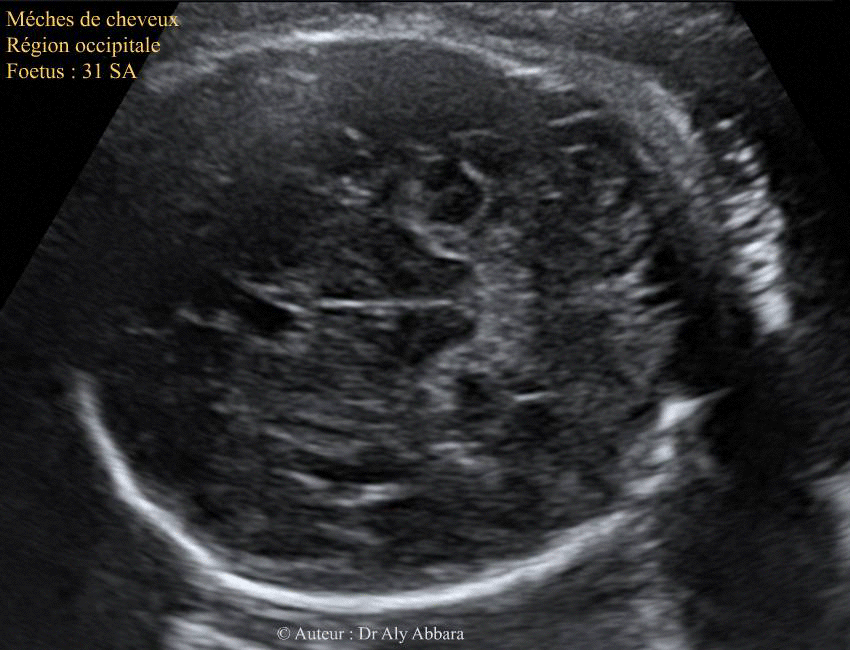

Meches De Cheveux Chez Un Fœtus De 31 Sa Possedant Une Chevelure Assez Fournie